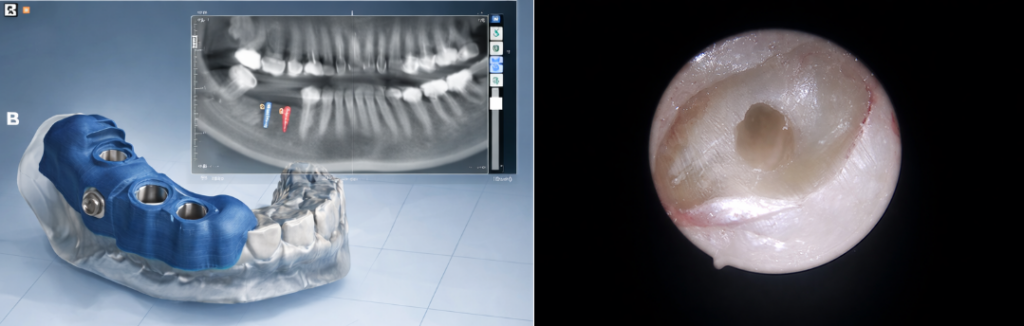

Ein besonderer Schwerpunkt unserer Praxis ist die geführte Implantologie

Dank modernster 3D-Planung und individuell angefertigter Bohrschablonen können Implantate exakt positioniert werden – sicher, präzise und minimalinvasiv.

Durch die digitale Planung wissen wir bereits vor dem Eingriff exakt, wo das Implantat gesetzt wird. So schaffen wir die Grundlage für langlebige, ästhetisch perfekte Ergebnisse – bei maximaler Sicherheit.

und die mikrochirurgische Wurzelspitzenresektion. Nach der Entfernung der entzündeten Wurzelspitze arbeiten wir mit starker Vergrößerung und moderner Endoskoptechnik. So können wir auch feinste Strukturen erkennen und sorgfältig behandeln – für eine möglichst sichere und langfristige Heilung.